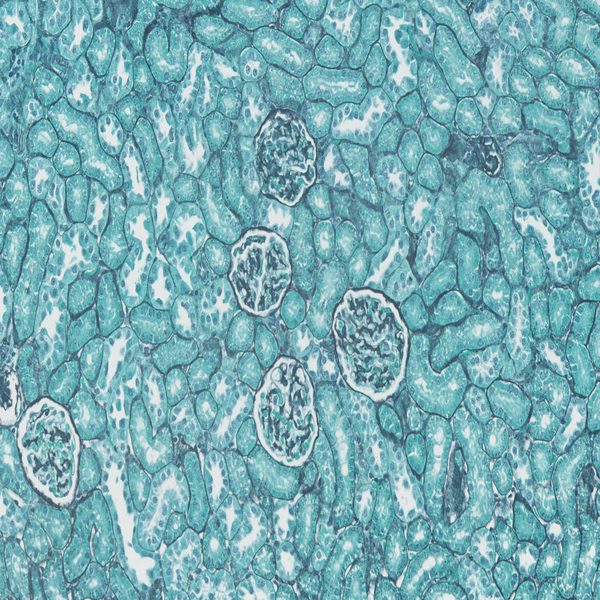

- Preparation of paraffin and frozen tissue sections in different sizes

- General and specialized tissue and cell staining

Histological methods includes sample processing in the pathology laboratory, preparation of the slide and its examination under a microscope, sample fixation, molding, microtome cutting, staining and assembly of the slides.